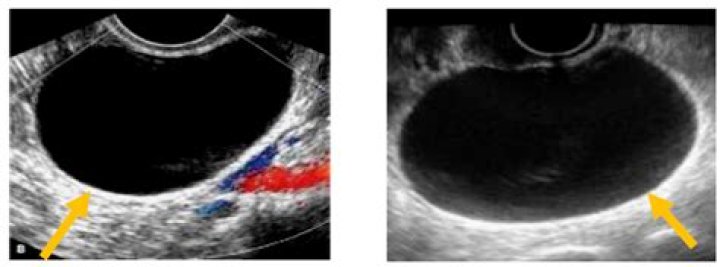

How do you know if a teratoma is cancerous?

Your doctor may also request tests such as: X-ray, ultrasound, bone scans, MRI, and CT to see where the tumor is and contain its spread. Blood tests to check hormone levels that may indicate the presence of a tumor. Biopsy to see if the teratoma is cancerous.